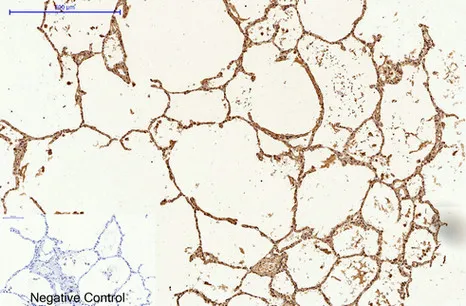

LC3A(5G10)Mouse Monoclonal Antibody

Cat: AMM13240

Size1:50μL Price1:$118

Size2:100μL Price2:$220

Size3:200μL Price3:$380

Application:WB,IF-P,IF-F,ICC/IF,IHC-P

Reactivity:Human,Rat,Mouse

Conjugate:Unconjugated

Optional conjugates: Biotin, FITC (free of charge). See other 26 conjugates.

Gene Name:MAP1LC3A